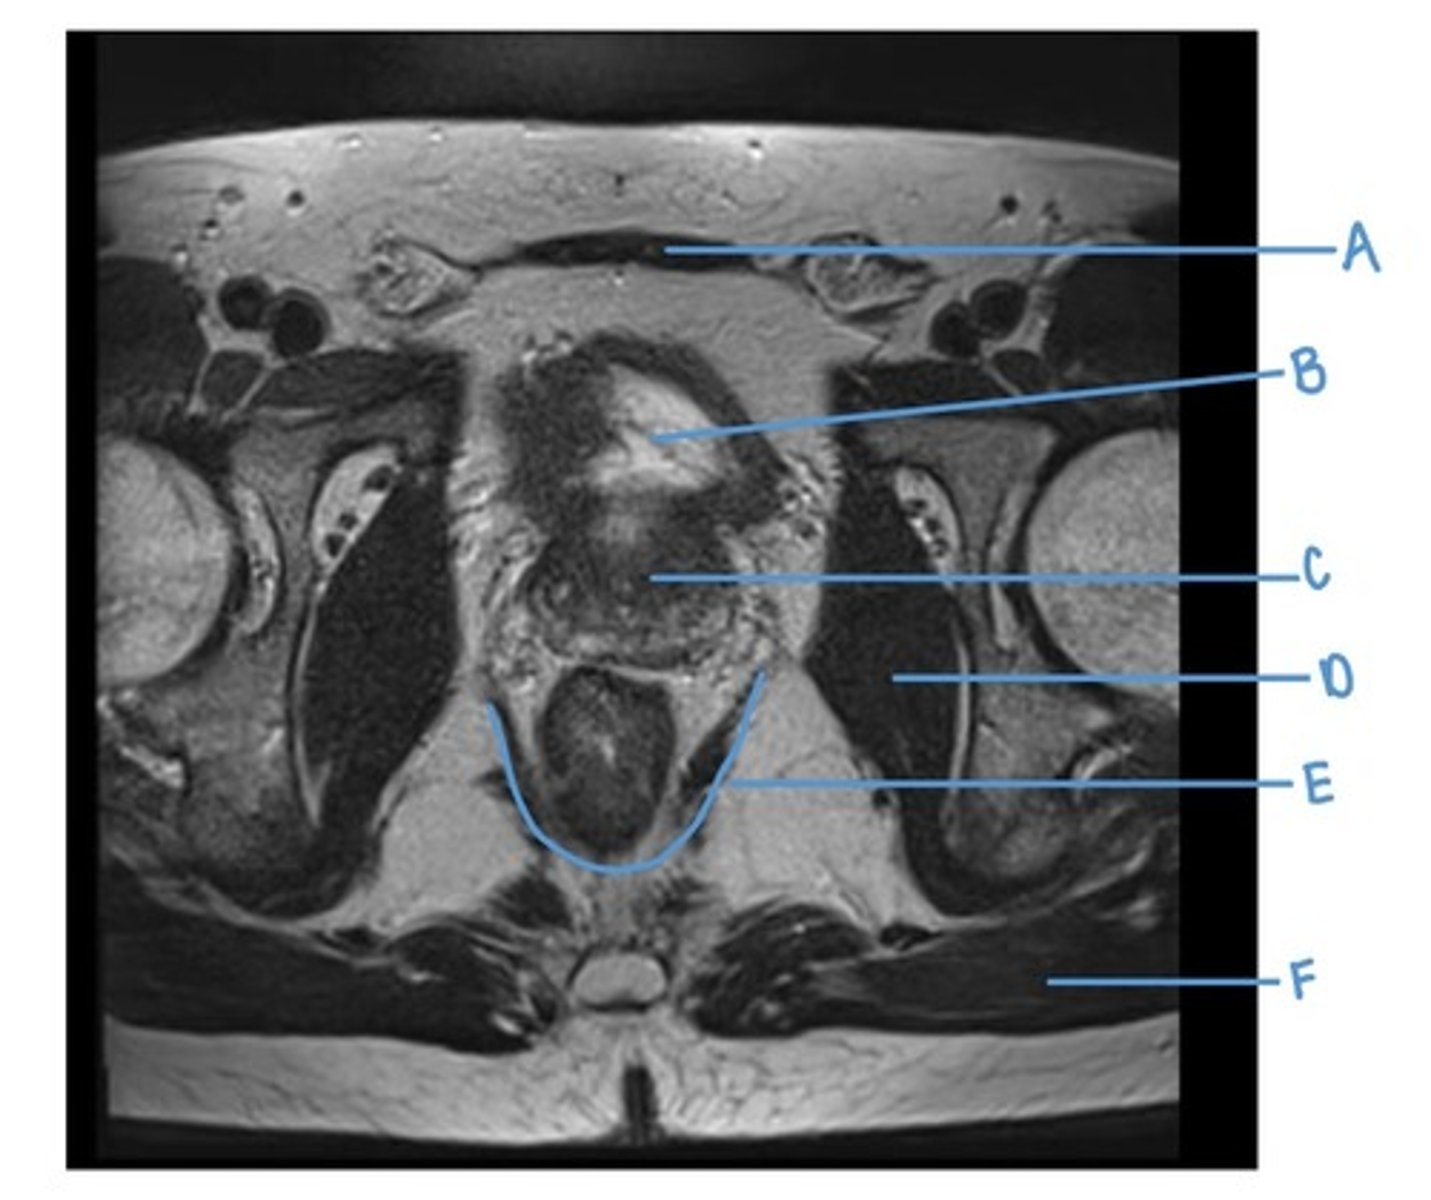

rectus abdominus muscle

A

bladder

B

prostate

C

obturator internus muscle

D

levator ani muscle (pubic diaphragm)

E

gluteus maximus muscle

F